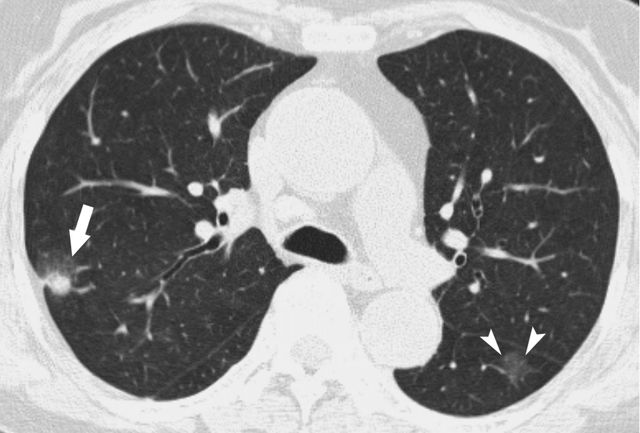

肺部结节通常是指肺内直径小于或等于3cm的类圆形密度增高影,可单发或多发,可以由许多原因引起,包括细菌感染、真菌感染、结核、肉芽肿等,也有一部分肺结节是肿瘤或癌前病变。虽然肺结节不等于肺癌,但是要判断它的性质也不容易。

箭头所指示为磨玻璃结节

箭头所指为部分实性结节